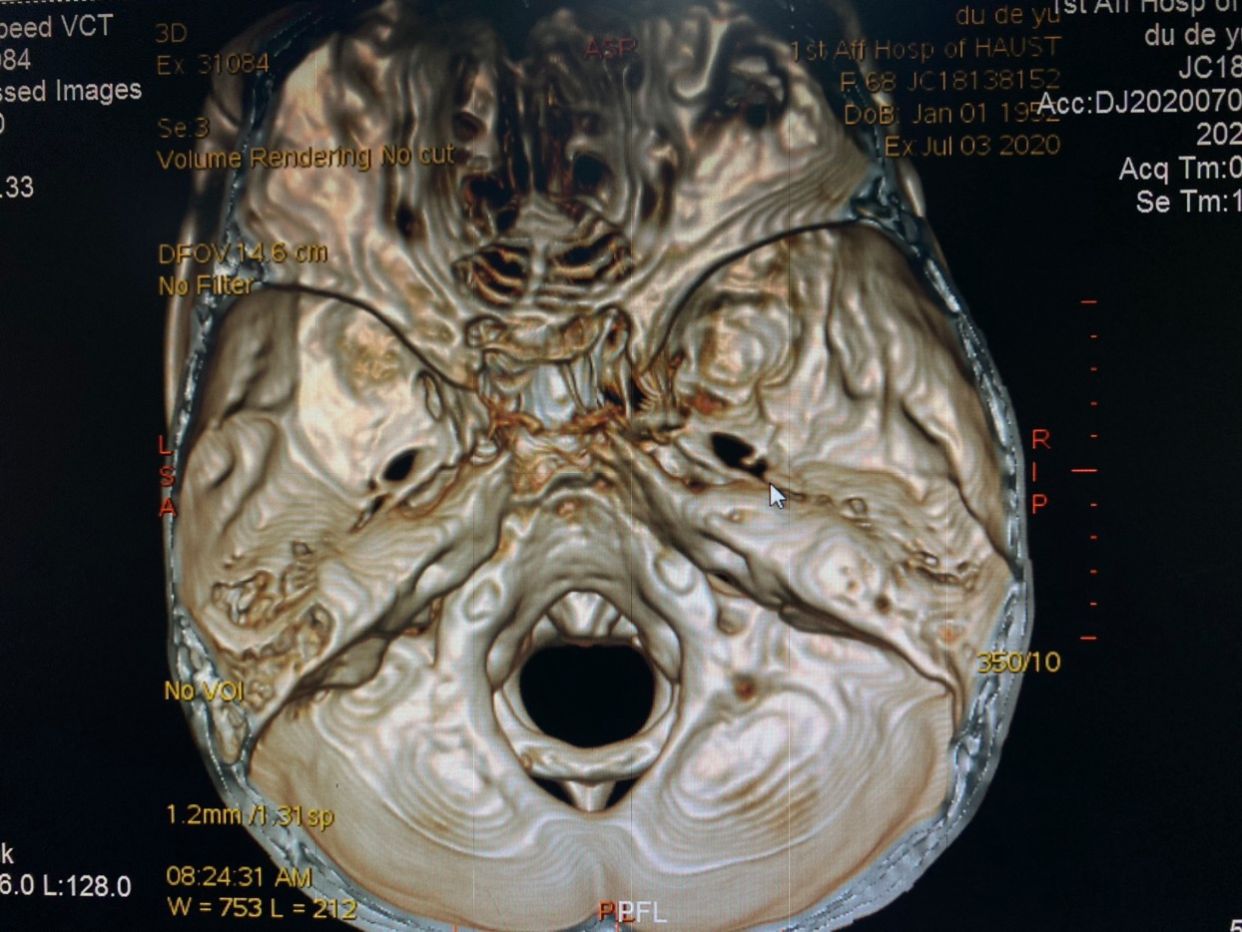

患者,女性,68岁,间断右侧颌面部疼痛40余年入院。查体:右侧V1-3支疼痛,累及右侧颞部头皮电击样疼痛。既往史:既往20年前行右侧三叉神经痛射频治疗两次,伽马刀治疗1次。术前行颅底CT检查,右侧卵圆孔破坏严重。

右侧卵圆孔内可见骨刺,增加手术难度(术中导管球囊被刺破以及进入麦氏囊腔困难)

卵圆孔与棘孔融合,如果穿刺针位置偏差,可刺破脑膜中动脉,引起出血可能。